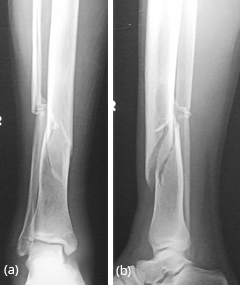

Generally occurs in children less than 10 years. Spontaneous regression is known. Any surgical correction leads to recurrence. Osteofibrous Dysplasia (OD) OD is another entity commonly involving the tibial shaft. Radiologically, an elongated lytic lesion with areas of sclerosis and anterior bowing of the tibia are classical features (Figure 2).

Figure 2a,b: Osteofibrous dysplasia of the tibia. Note the lytic and sclerotic changes scattered. Anterior bowing of the tibia is a characteristic finding.